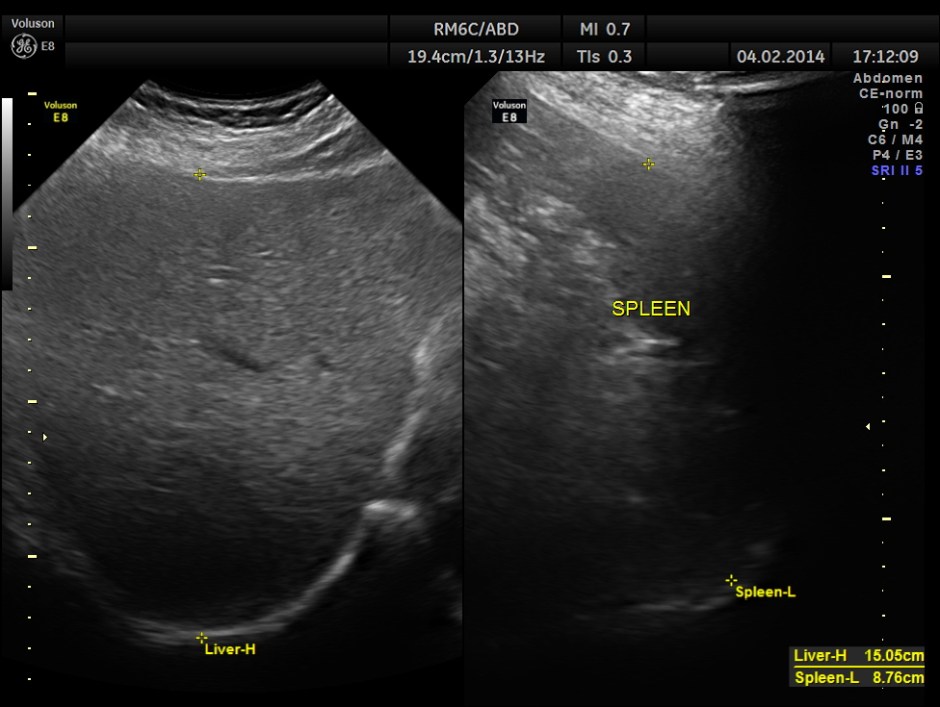

This was a 63-year-old gentleman who came for recurrent episodic right upper quadrant pain of 2 to 3 weeks duration.On examination Murphy’s sign was positive. The pictures follow.

The pancreas appeared to be normal.

He came for a repeat scan 50 days later.

The C.B.D. measured 5.70 mms ( still within the normal range ).There was no evidence of any obstruction .